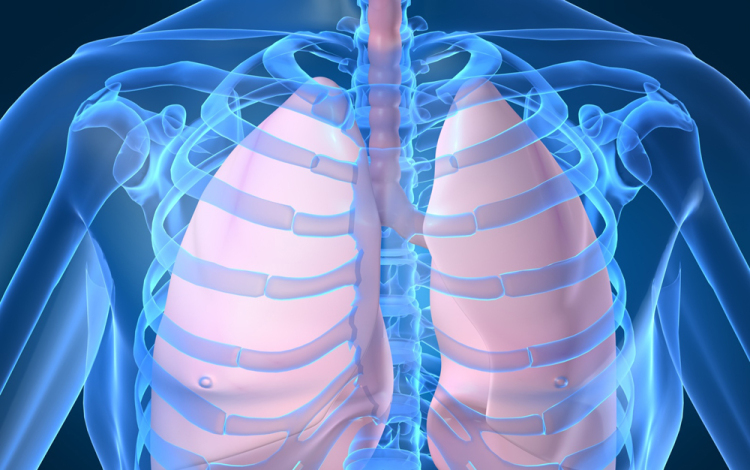

Húszan várnak tüdőátültetésre Magyarországon

Húszan várnak tüdő-transzplantációra az országban, tavaly 12 magyar betegen hajtottak végre ilyen szervátültetést külföldön

- mondta Kásler Miklós, az Országos Onkológiai Intézet főigazgatója vasárnap az M1 aktuális csatorna esti műsorában. A főigazgató ezt azzal kapcsolatban közölte, hogy még idén elvégezhetik az első tüdőátültetést Magyarországon.

Magyarországról tavaly 37 tüdőt szállítottak Bécsbe átültetési céllal; ha nálunk is elérhetővé válik a műtét, akkor várhatóan a környező országokból is Budapestre érkezik majd a betegek egy része Bécs helyett - mondta a főigazgató.